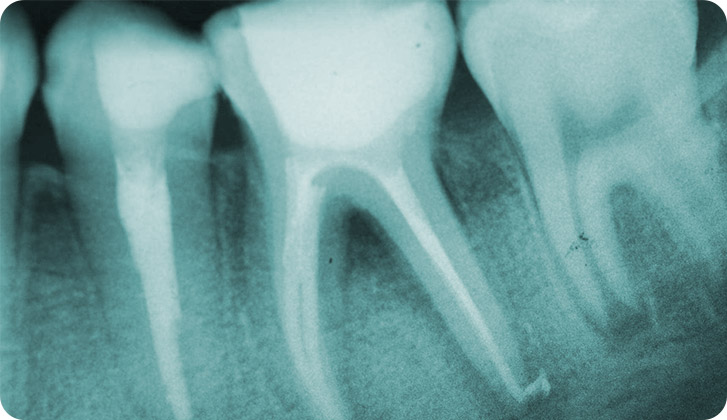

Rama de la odontología que se encarga del diagnostico y tratamiento de las enfermedades del tejido pulpar (vasos y nervios) del diente.

Clínicamente el paciente presenta sintomatología con dolor provocado o dolor espontaneo, sensibilidad debido a inflamación, algunos tipos de abscesos provocados por procesos infecciosos.